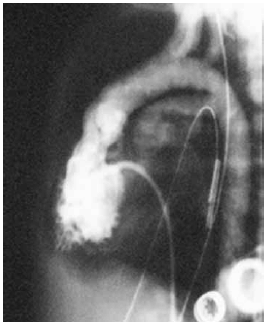

Observe a imagem.

Essa ventriculografia representa a seguinte cardiopatia congênita: